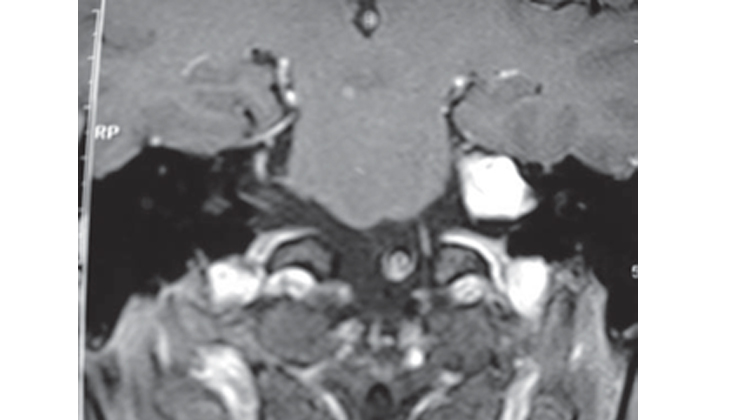

Akustik nörinom denge sinirinden köken alan iyi huylu bir tümördür. Tümör oldukça yavaş olarak büyür ve çevre dokulara bası yapabilir. Hastalarda tek taraflı kulak çınlaması ve işitme kaybı, dengesizlik şikayetleri daha ön plandadır. Şiddetli baş dönmeleri çok enderdir. Baş dönmesinden ziyade dengesizlik şeklinde ortaya çıkar. Yüz felci görülebilir. Tanı MR ile konulur.</span></div></div>